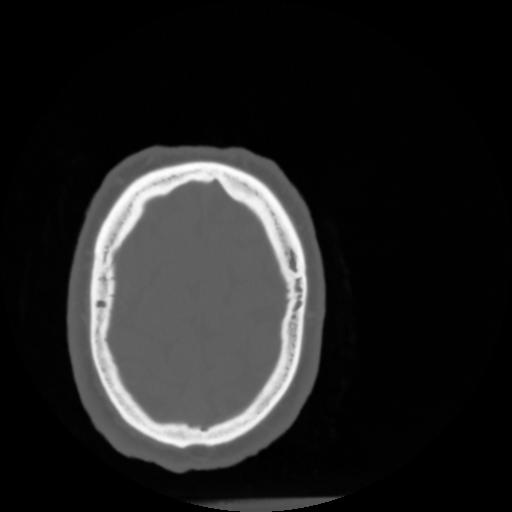

4 CEREBRO,,Vol,0.5,CEREBRO,,